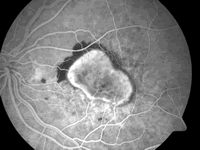

AMD可引起严重且不可逆的视力丧失,患者视网膜异常血管增生、渗出,最终影响中心视力,是55岁以上人群的主要致盲原因。湿性AMD占所有AMD的10%,大多数未经治疗的湿性AMD患者视功能受损,80%伴随的视力丧失归因于湿性AMD。

Ranibizumab具有阻止新生血管增生及渗出的作用。3项多中心、随机研究显示,眼内注射ranibizumab治疗AMD安全有效。患者每月接受1次眼内注射,共12个月,几乎95%患者的视力得以维持(其中1/3的患者视力改善),对照组约为60%。一项使用ranibizumab对患者进行24个月治疗的研究表明,患者视力仍保持稳定。